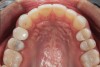

(4.) Preoperative occlusal view of upper arch.

Figure 4

A comprehensive examination was carried out, and preoperative photographs were taken (Figure 1 through Figure 4). The patient presented with fair oral hygiene and slight, generalized tissue inflammation. Caries and defective restorations were detected on teeth Nos. 4, 5, 13, and 14. The crown on tooth No. 12 was showing signs of leakage, and although the endodontic access cavity had been temporarily restored with composite, this endodontic re-treatment was acceptable and the tooth was otherwise symptom-free. Erosion was present on most of the posterior teeth and the cuspids, and abrasion was noted on teeth Nos. 4, 5, 10, 11, 20, 21, 22, 28, and 29. An examination of the patient's muscles, joints, and bite revealed no joint sounds, a normal range of motion, and negative joint load and immobilization tests.

The patient's removable dental orthotic covered the lower bicuspids and first molars. With the orthotic in place, there was shim stock contact on all posterior teeth and on the second molars that were not covered by the appliance. However, there was no incisal overlap and a lack of anterior guidance.11 When the orthotic was removed, solid shim stock contacts were present on the second molars and the right lateral incisor. These contacts were reproduced every time the appliance was removed. The same contacts were found on the patient's mounted models, which confirmed that the joints were in centric relation. Whether the lower second molars had overerupted as a result of wearing the appliance or had already been in this position before the orthotic was fitted could not be established. Apart from these three contacts, no other teeth touched, and there was a 2-mm space between the posterior teeth, making mastication difficult. Interestingly, wear facets were present on the palatal surfaces of the upper central and lateral incisors, indicating that at some point in time, there had been significant overlap of the anterior teeth and a possible constriction of the chewing envelope. Analysis of a cephalometric radiograph showed a class II growth tendency with a reduced mandibular plane angle, which supported the theory that the patient had at one time possessed a class II occlusion.